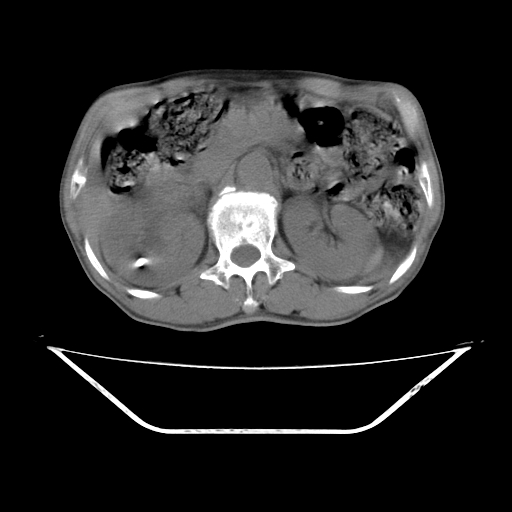

平扫

考虑右肾盂癌,肾动脉受侵,右肾功能减退,右肾盂输尿管积水,管壁增厚,考虑种植转移,应该把下面扫完的

支持右侧肾盂癌伴肾静脉瘤栓形成可能性大,右肾结石.肝右叶后段低密度影,不除外转移.

右肾囊实性占位,支持肾癌,窗宽窗位不是很理想

右肾盂旁ca并肾静脉瘤栓形成/肾功能降低。

右肾结石。

支持 右侧肾盂癌伴肾静脉瘤栓形成可能性大,右肾结石;肝右叶后段低密度影,不除外转移。

1.右侧肾盂癌伴肾盂积水。

2.肾脏功能减退,原因有:(1)肾动脉受侵。(2)肾静脉受侵(3)肾积水,等。本例,肾动脉显影较好,但受压明显;肾静脉无明显显示,受压或静脉癌栓,下腔静脉腔内未见明显充盈缺损。